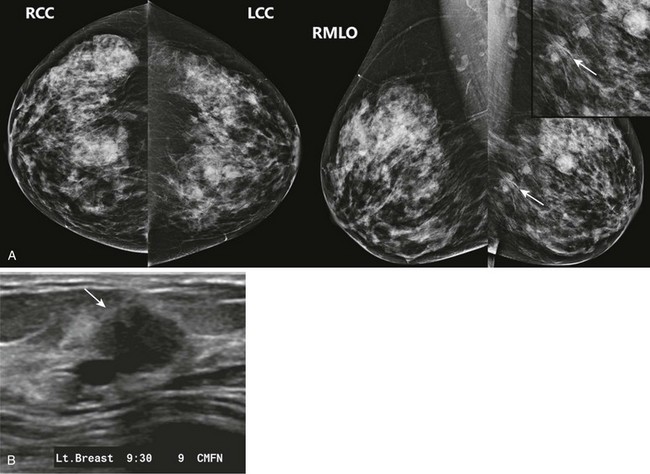

FIGURE 8-8 Multiple Masses and One-View Asymmetry Due to IDC.

A, Screening mammogram on a 64-year-old woman shows multiple bilateral masses. There is an irregular one-view asymmetry in the posterior left breast (arrows). B, US reveals a corresponding solid mass with microlobulated margins (arrow). Multiple cysts were also seen. Core biopsy revealed IDC.